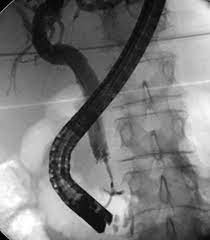

- Imaging: Imaging techniques such as ultrasound, CT scans, MRIs, and PET scans are essential for identifying the tumor’s location and assessing whether it has spread to nearby structures or distant organs.

- Endoscopic retrograde cholangiopancreatography (ERCP): This procedure can help diagnose blockages in the bile ducts and provide biopsy samples to confirm the presence of cancer.